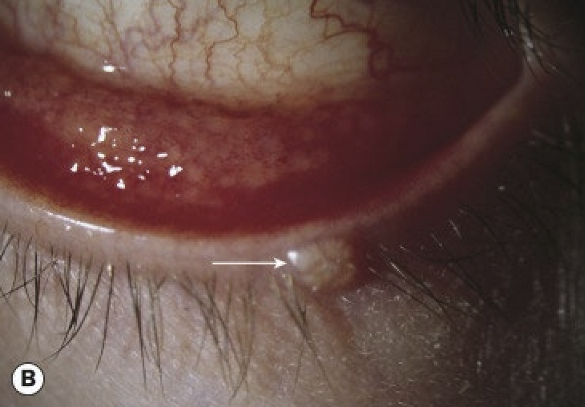

What is the typical age of incidence for molluscum contagiosum?

Most commonly affects children between 2–4 years of age. Molluscum lesions are typically seen along the eyelid margin.

<p>Most commonly affects children between 2–4 years of age. Molluscum lesions are typically seen along the eyelid margin.&nbsp;</p>

What are the symptoms and presentations of molluscum contagiosum conjunctivitis?

• Chronic unilateral ocular irritation

• Pale, waxy, umbilicated nodule on the lid margin

• bulbar conjunctival nodule (seen with immunocompromised patients)

• Epithelial keratitis and pannus can be seen in longstanding untreated cases

<ul><li><p>Chronic unilateral ocular irritation&nbsp;</p></li><li><p>Pale, waxy, umbilicated nodule on the lid margin</p></li><li><p>bulbar conjunctival nodule (seen with immunocompromised patients)&nbsp;</p></li><li><p>Epithelial keratitis and pannus can be seen in longstanding untreated cases</p></li></ul><p></p>